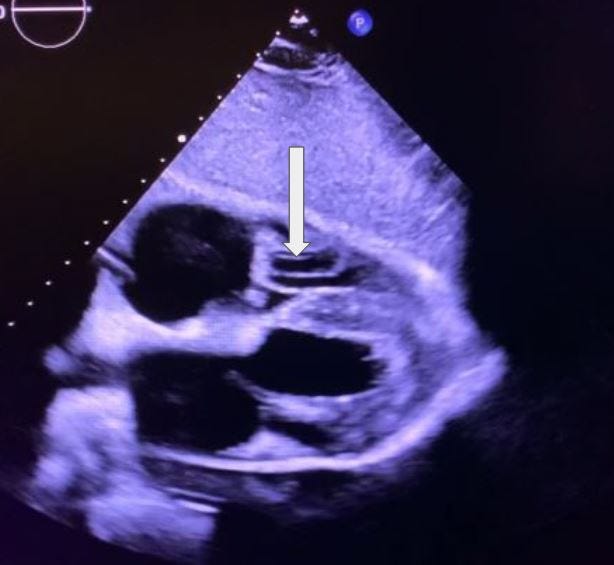

What is the structure being indicated in this subcostal 4-chamber view?

A. Tricuspid valve

B. Chordae tendineae

C. Septum

D. Pulmonary vein